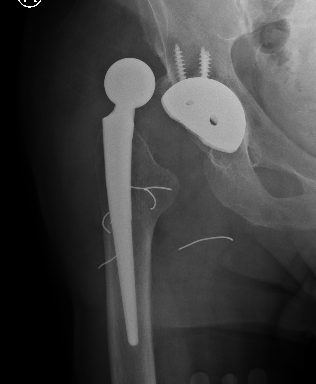

Dislocated constrained liner

Successful reduction constrained liner

Unsuccessful reduction constrained liner